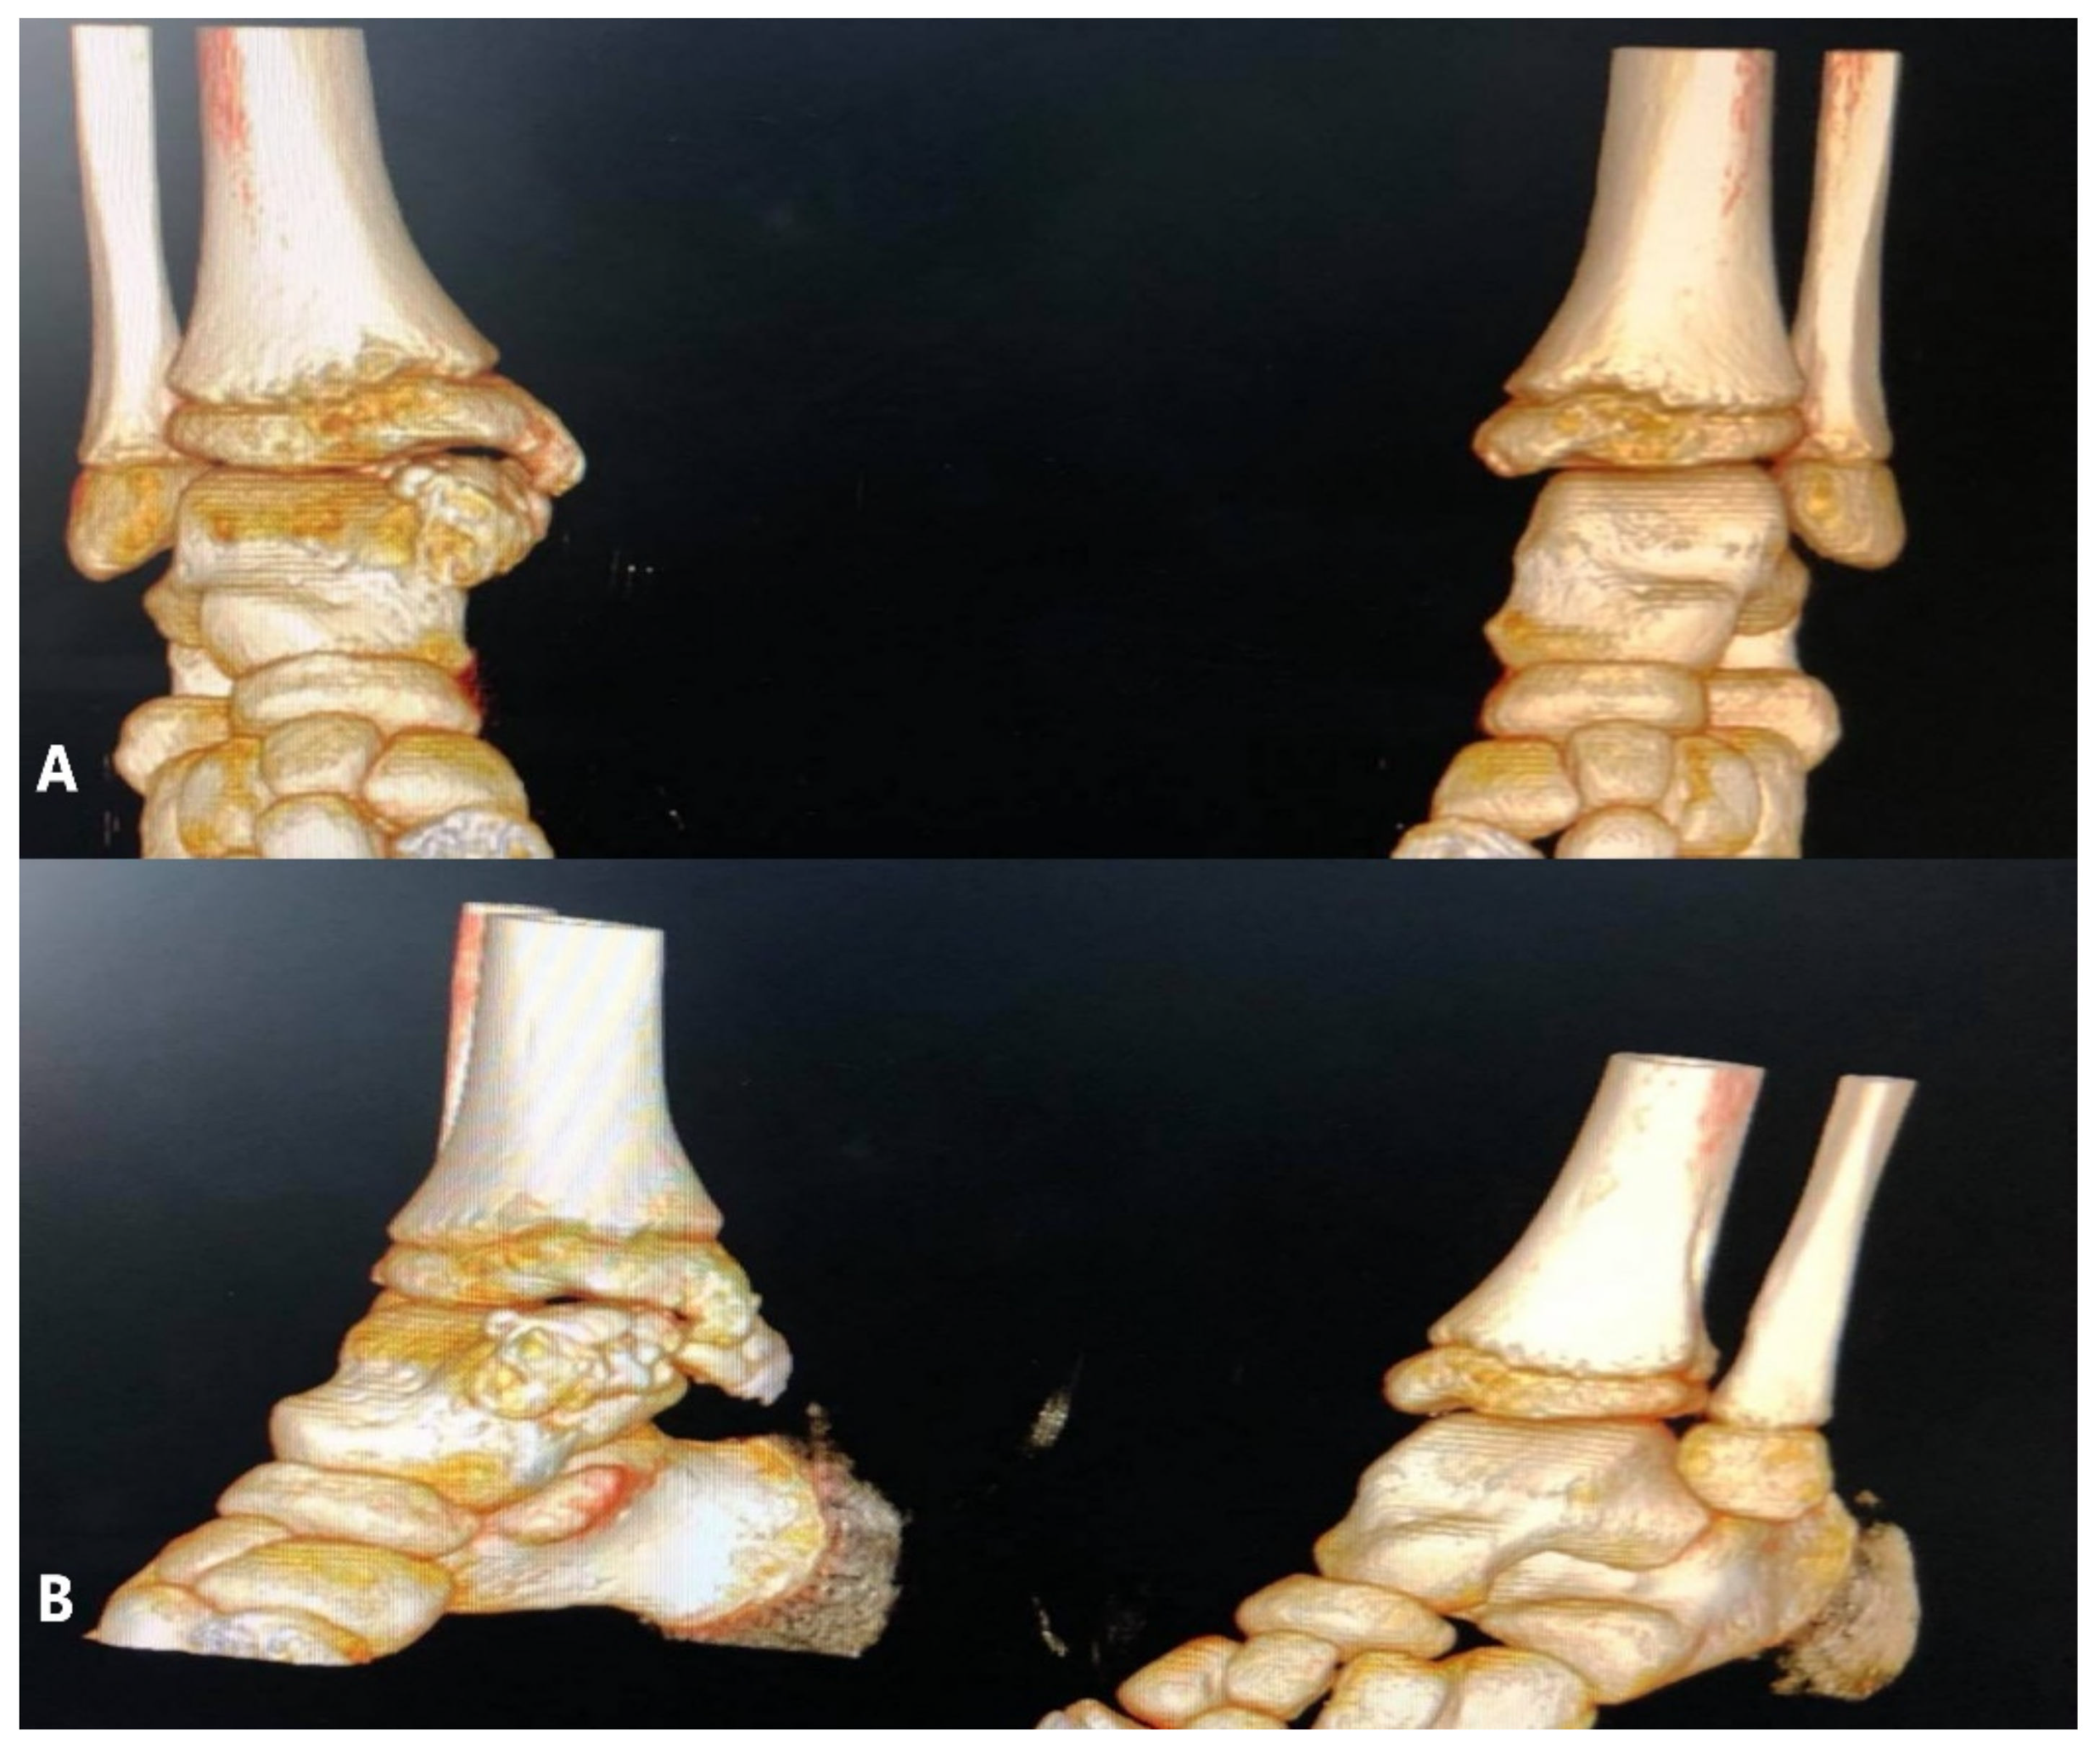

The patient underwent further investigations, such as CT scan and MRI of the right ankle (Figure 3, Figure 4 and Figure 5). The results suggested the presence of an osteochondral mass formed by multiple centers, well separated from the talus and the tibia. CT: computed tomography, MRI: magnetic resonance imaging

Figure 3. CT images—(A,B)—coronal slice, left, and right ankle; (C,D)—transverse slice—left and right ankle; images showing multiple centers of endochondral ossification near the right talus.